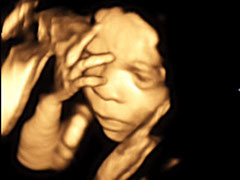

Hier zeigt ein kleiner Film einen 4D-Ultraschall

Klicken, um den Film zu sehen

Baby 4D UltraschallBaby 4D UltraschallBaby 4D UltraschallBaby 4D UltraschallBaby 4D UltraschallBaby 4D UltraschallBaby 4D UltraschallBaby 4D UltraschallBaby 4D UltraschallBaby 4D UltraschallBaby 4D UltraschallBaby 4D Ultraschall4 - 6<>